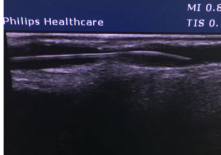

附图

(三) 手术前后血管对比示意图